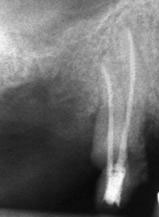

Ако при диагностична рентгенография се установи, че даден канал не е запълнен до физиологичното стеснение, е необходимо да се проведе повторно ендодонтско лечение.

В някои случаи недобре запълненият коренов канал е показание дори за отстраняване на протезни конструкции (корони и мостове) в които е включен съответният зъб.

Понякога е налице патологичен процес около апекса на зъба, който налага да се проведе допълнителна хирургична намеса с цел отстраняване на лезията.